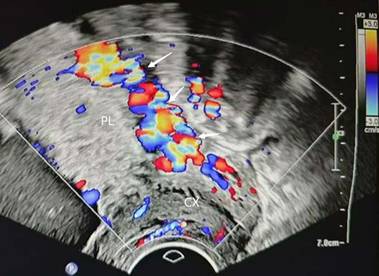

Ultrasound (US) and magnetic resonance imaging (MRI) have shown high diagnostic performance in the detection of PAS[17-19]. Ultrasound serves as the primary diagnostic tool for PAS; however, current clinical sonographic criteria are primarily validated for anterior PAS cases complicated by placenta previa. When the placenta invades the posterior uterine wall, the diagnostic accuracy of prenatal ultrasound in detecting characteristic signs remains uncertain[17, 18, 20]. Dellapiana et al. reported that the application of standard sonographic criteria results in a low antenatal detection rate for posterior PAS[21]. For optimal ultrasound diagnosis of posterior PAS, the recommended gestational window for initial screening is between 25 and 28 weeks. This timing is advantageous because: the uterine wall and placental architecture are more clearly visualized at this stage, the amniotic fluid-to-fetal size ratio is more favorable, and the posterior implantation site becomes more accessible for evaluation[22]. The ultrasound markers of PAS include: (1) Loss or irregularity of the hypoechoic area between the uterus and placenta, the 'retroplacental clear zone' (Figure 1), (2) Myometrial thickness <1mm, (3)placental lacunae with high velocity flow (>15cm/s) (Figure 2), (4)Thinning or interruption of the uterine serosa-bladder wall interface, (5) Placental bulge, (6) Exophytic mass,(7) Subplacental and/or uterovesical hypervascularity, (8) Loss of vascular arch parallel to the basal plate and irregular intraplacental vascularization (Figure 3)[3, 23]. After excluding the two bladder line-dependent criteria, the following four key sonographic features were consistently observed in the posterior placental region: loss or irregularity of the hypoechoic area between the uterus and placenta, myometrial thickness <1mm, placental lacunae with high velocity flow (>15cm/s), and Loss of vascular arch parallel to the basal plate and irregular intraplacental vascularization[22]. Many authors have adopted a two-criteria system in their articles: PAS is diagnosed when there are two or more ultrasonic signs present[22, 24]. The two-criteria system has a high sensitivity (60.0%), specificity (98.9%), and positive predictive value (85.7%). Moreover, when using a single criterion or the optimal criterion, there is no improvement in the maternal outcomes of true positive and false negative cases, which confirms the reliability of the two-criteria system[22]. A retrospective study has found that the sensitivity of ultrasound in detecting anterior PAS is as high as 81 - 93%[18]. Other studies have also validated this discrepancy. The ADoPAD (Antenatal Diagnosis of Placental Attachment Disorders) Study Group reported that prenatal ultrasound detected 92% of all anterior PAS cases, which was significantly higher than the 62% detection rate for posterior PAS[11]. The detection rates of PAS in anterior and posterior placentas were reported by Pilloni et al. as 89.7% and 50% respectively, under the application of the two - criteria system[24]. However, in a recent study, after excluding patients with placenta previa, only 30% of posterior placenta PAS cases were diagnosed through prenatal ultrasound screening. This suggests that compared with anterior PAS, ultrasound examination has lower sensitivity for posterior PAS[21]. An independent evaluation of the sensitivity of individual ultrasound signs for pathologically confirmed posterior and anterior PAS was conducted. The sensitivities of retroplacental lacunae, vascular congestion, myometrial thinning, and absence of hypoechoic areas in detecting posterior wall PAS ranged from 24% to 42%. However, multiple studies have demonstrated that the absence/irregularity of the retroplacental clear zone shows the highest sensitivity and negative predictive value for posterior placenta accreta - comparable to or even exceeding that of the dual-criteria system. These findings confirm the diagnostic importance of this specific criterion for posterior placenta accreta, while other criteria exhibit significantly lower sensitivities compared to the dual-criteria system[22, 24]. This divergence primarily stems from hemodynamic differences, as the posterior uterine wall's lower segment demonstrates greater vascularity compared to the anterior wall. Sonographically, the retroplacental clear zone shows better echogenic contrast with posterior placental positioning than with anterior implantation. Consequently, when placental invasion disrupts the retroplacental clear zone's integrity, sonographic abnormalities become more detectable on the posterior uterine wall. This diagnostic advantage is most evident between 26 and 28 weeks of gestation[24]. In summary, ultrasound demonstrates suboptimal sensitivity for detecting posterior PAS. As the first-line imaging modality, its diagnostic performance is limited by three key factors: (1) operator-dependent variability, (2) reduced efficacy in obese patients, and (3) poor detection of posterior placental invasion. These limitations collectively compromise both the accuracy and clinical utility of ultrasound for posterior PAS diagnosis. Furthermore, current research on posterior PAS remains constrained by small sample sizes, highlighting the need for larger-scale studies to validate existing findings[22].

Figure 2

placental lacunae (arrow). PL, placenta. CX, cervix